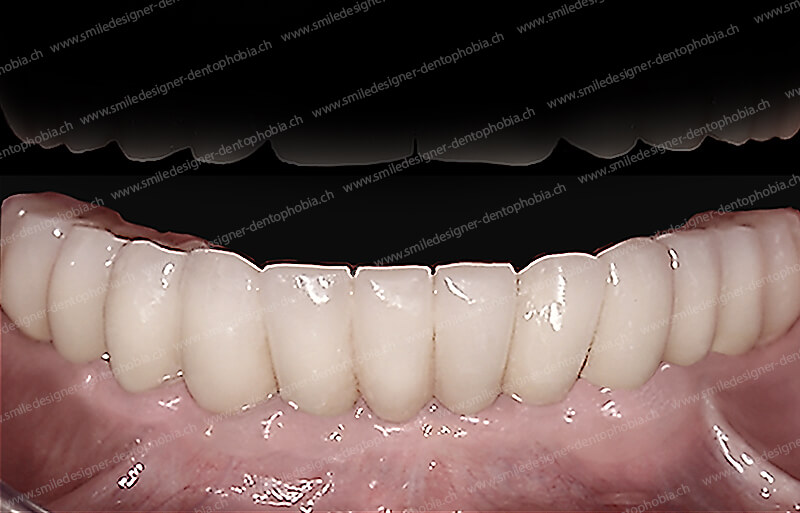

- Bridge définitif en céramique :

- Remplace le bridge provisoire après ostéo-intégration complète des implants.

- Esthétique supérieure (transparence, couleur naturelle) et résistance accrue pour une mastication optimale.

- Esthétique naturelle : fausse gencive en céramique et couronnes mimétiques pour un rendu invisible.